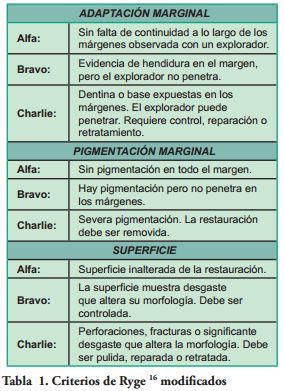

Adaptación Marginal, Pigmentación Marginal y Superficie, fueron las variables estudiadas para establecer la calidad de las restauraciones, siguiendo el criterio de Ryge, (16) modificado por los autores (Tabla 1).

Los Criterios de Éxito (CE) fueron definidos por los autores, de acuerdo al criterio de Ryge modificado y a lo establecido por Anusavice (17) y agrupados de la siguiente manera: